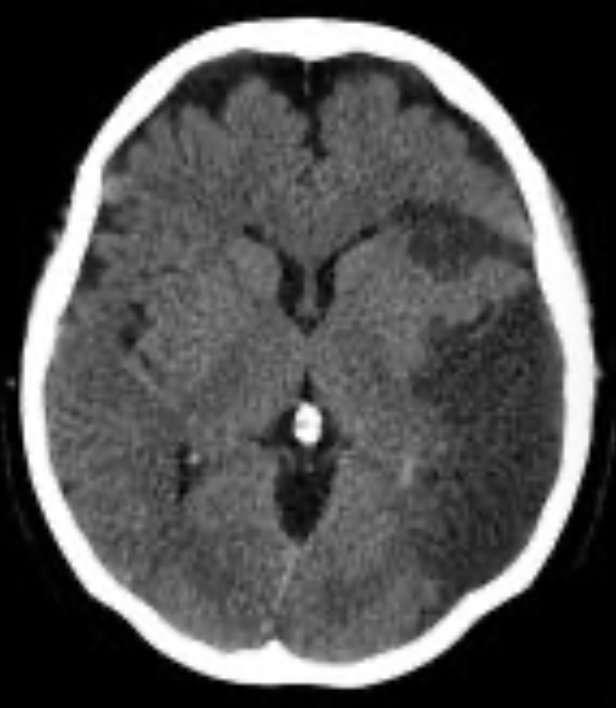

EVC hemorragico

Hipertensivo